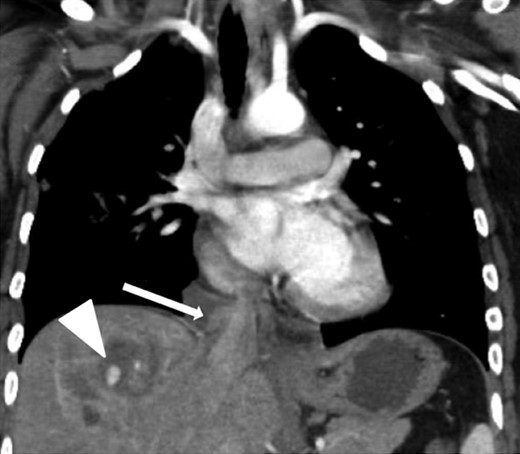

Coronal contrast-enhanced CT of the chest showing abnormal contour of the supradiaphragmatic IVC with ventrally and laterally confined contrast extravasation (arrow) consistent with a pseudoaneurysm surrounded by pericaval hematoma as well as a segment 8 hepatic hypodensity consistent with liver laceration and focal area of contrast extravasation (arrowhead).

Coronal contrast-enhanced CT of the abdomen performed 30 min after the initial CT of the chest showing persistence of the abnormal contour of the supradiaphragmatic IVC with contrast extravasation confined laterally and ventrally (arrow), nonexpanding pericaval hematoma and a segment 8 hypodensity (arrowhead) consistent with liver laceration.